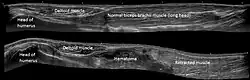

The proximal tendons of the biceps brachii are commonly involved in pathological processes and are a frequent cause of anterior shoulder pain.[18] Disorders of the distal biceps brachii tendon include insertional tendonitis and partial or complete tears of the tendon. Partial tears are usually characterized by pain and enlargement and abnormal contour of the tendon.[19] Complete tears occur as avulsion of the tendinous portion of the biceps away from its insertion on the tuberosity of the radius, and is often accompanied by a palpable, audible "pop" and immediate pain and soft tissue swelling.[20]

A soft-tissue mass is sometimes encountered in the anterior aspect of the arm, the so-called Reverse Popeye deformity, which paradoxically leads to a decreased strength during flexion of the elbow and supination of the forearm.[21]

Tendon rupture

Tears of the biceps brachii may occur during athletic activities, however avulsion injuries of the distal biceps tendon are frequently occupational in nature and sustained during forceful, eccentric contraction of the biceps muscle while lifting.[20]